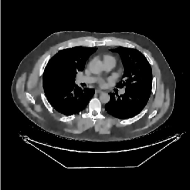

This section compares the generalization capabilities between the proposed MBIR method, PWLS-ST-, and a denoising deep NN, FBPConvNet [14], that are trained from the phantom data; in particular, we tested the trained PWLS-ST- and FBPConvNet models to phantom and clinical scan data. The results in Fig. 6 show that the non-MBIR FBPConvNet method has higher overfitting risks, compared to the proposed PWLS-ST- MBIR method. When tested on clinical scan data, PWLS-ST- achieves much more accurate reconstruction, compared to FBPConvNet. See Fig. 6(b). When tested on phantom data, FBPConvNet generates more unnatural features as the number of views reduces, although it gives lower RMSE values compared to PWLS-ST-. See zoom-ins in Fig. 6(a). The FBPConvNet results above correspond to those in the recent work [16] that FBPConvNet [14] generated some unexpected structures.